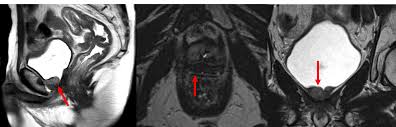

Advanced prostate cancer, also called metastatic cancer, means the cancer has spread to other areas of your body beyond your prostate gland. When psa levels rise above 0.2 ng/ml, the cancer is considered recurrent. Meanwhile, if the recurrence rate is high, then most probably the tumor will involve the adjacent. The location of the recurrence is determined by these radiographic scans. You might need treatment if it rises. A sign that your cancer may have returned is if your psa level has risen by 2ng/ml or more above its lowest level. Even when prostate cancer returns, most survive. Cancer that seems to return quickly may have become resistant to treatment, so it's. Prostate cancer can recur locally in the pelvis or elsewhere in the body. It usually takes more than one elevated psa test to determine that prostate cancer has returned. If the cancer is found in another part of the body, the recurrent cancer is considered metastatic. Recurrence is cancer that goes away and comes back, while progression is cancer that worsens or spreads. But of that 30 percent, only about a third will end up with a cancer recurrence.